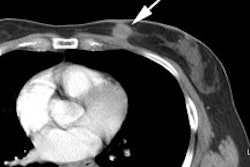

Bladder cancer: Dilute urinary activity in this patient's bladder allowed accurate detection of their bladder cancer (white arrows on CT, black arrows on PET scan). In general, urinary excretion of FDG limits evaluation of urinary tract malignancies, however, hydration and diuresis can improve diagnostic accuracy. |

|

|